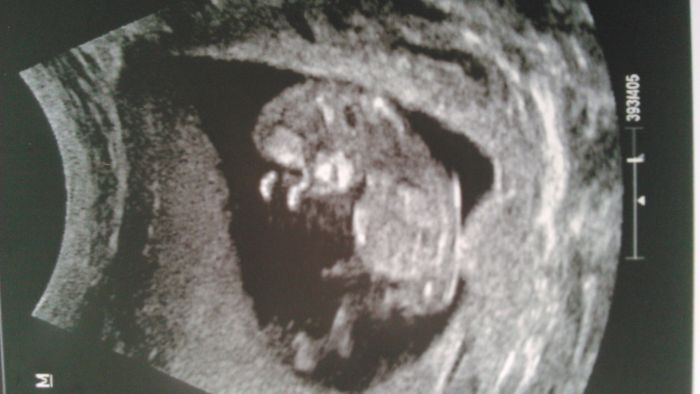

Ahoj holky, tak jsme taky po kontrole - Broucek se ma k svetu, skoro ho neslo vyfotit, jak se tam mlel a krasne vyrostl. Nakonec uz neni dle utz o tyden mladsi, ale velikosti odpovida stari dle pm , 12+1 ( popravde nerozumim, jak to pocitaji, mne k dnesnimu dni dle mistni kalkulacky vychazi 11+6...). Vyridila se i neschopenka, jenom prevest diagnozu neslo, ale jsem moc rada i za novou, hlavne, ze nemusim resit vypoved v praci. Jediny problem je to, ze jsem zhubla, sice jen 2kg, ale pri me standartni (pod)vaze je to problem, strasi me nemocnici....Tak snad uz nevolnosti prejdou a ja se konecne v klidu najim :). V pondeli nas ceka screening, tak snad bude vse ok, po te kontrole jsem mnohem klidnejsi.

Posilam fotecku a preju vsem jen same dobre zpravy !